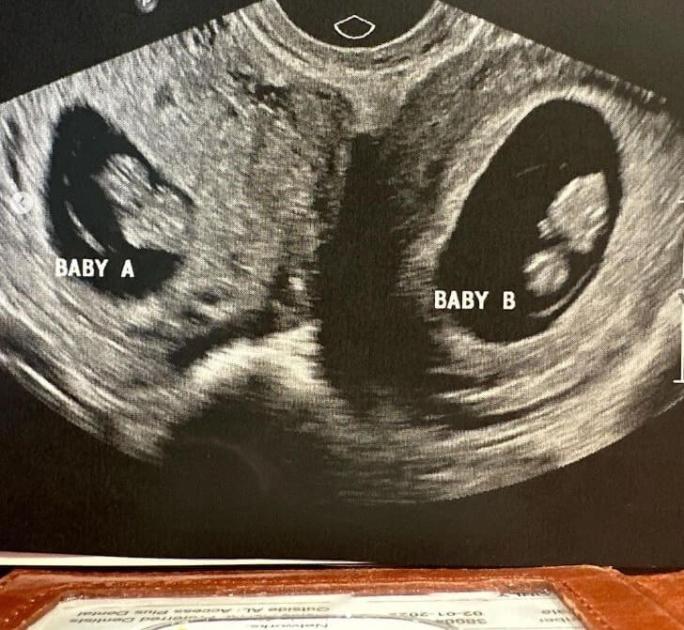

მაისში, ორსულობის მერვე კვირაზე, ულტრაბგერაზე ვიზიტისას, სამი შვილის დედამ შეიტყო, რომ ის არა მხოლოდ ტყუპებს ელოდებოდა, არამედ უფრო მეტიც — ნაყოფი ორივე საშვილოსნოში იყო წარმოდგენილი.

„გავოგნდით, მაგრამ შემდეგ ძალიან ბევრი ვიცინეთ“, — წერს კელესი.